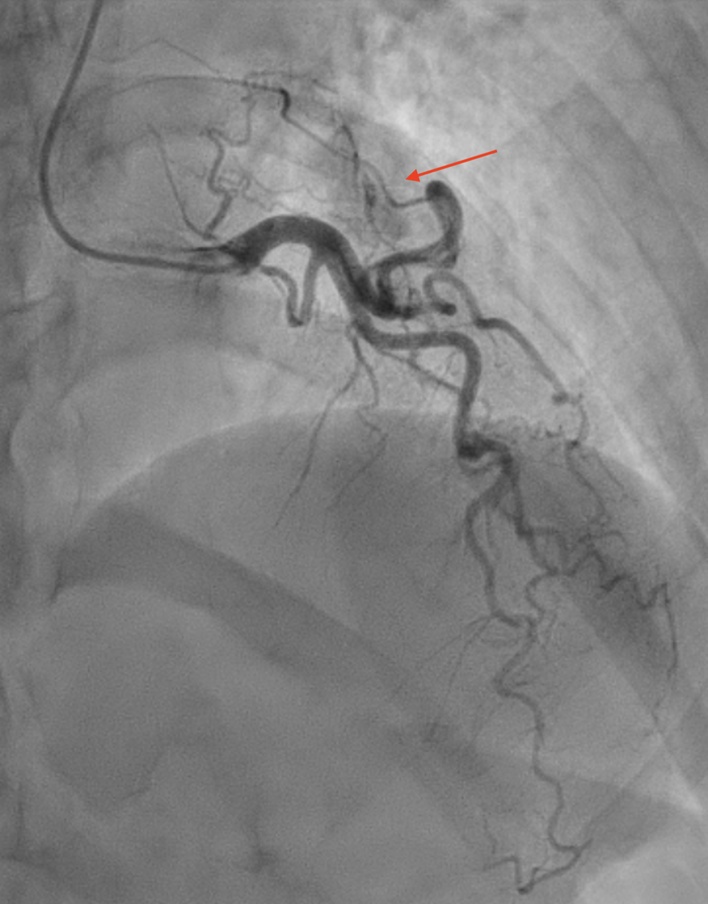

Coronary angiography showed very tortuous coronary arteries with three fistulae from the left anterior descending, left circumflex and right coronary arteries, all terminating in the pulmonary artery (figures 1–3). There was no evidence of obstructive coronary artery disease. Initial presumed diagnosis was myocardial infarction due to coronary steal syndrome. Cardiac magnetic resonance (CMR) imaging was performed. A standard protocol of white blood and cine image sequences with late gadolinium enhancement was used. Shunt assessment via formal volumetric analysis and flow analysis through the valves was performed. True forward stroke volume through the aortic valve was 99 ml/beat with a peak gradient across the valve of 8 mmHg and a regurgitant fraction of 1%. True forward flow through the pulmonary valve was 102 ml/beat. This confirmed that there was no significant shunt. Normal biventricular size and function, with no prior infarction, was also demonstrated. There was a small concentric pericardial effusion with a focal region of inferolateral epicardial fibrosis, suggesting a diagnosis of myopericarditis. The patient was treated with regular colchicine for three months, and ibuprofen, as required. Her troponin and symptoms settled and she was discharged.